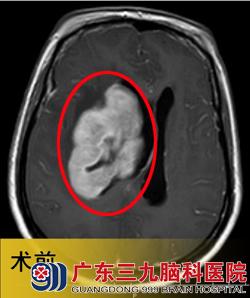

入院见潘女士呈嗜睡状,不能言语,四肢乏力。头颅磁共振检查见右基底节占位性病变,初步考虑为淋巴瘤。www.999brain.com

入院3天后,潘女士在广东三九脑科医院接受了“右侧基底节占位性病变取病理活检术+去骨瓣减压术”,术后病理结果为:弥漫大B细胞淋巴瘤。术后第4天,予以抢救性全脑放疗,并同步化疗。2012年11月4日复查头颅CT见右侧基底节病灶明显缩小,中线回位,遂继续予以全脑及局部残留肿瘤放疗。www.999brain.com